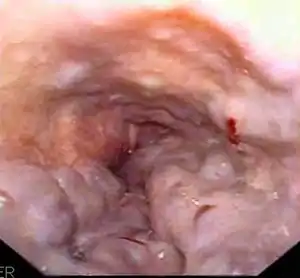

Esophageal varices are extremely dilated sub-mucosal veins in the lower third of the esophagus.[1] They are most often a consequence of portal hypertension,[2] commonly due to cirrhosis.[3] People with esophageal varices have a strong tendency to develop severe bleeding which left untreated can be fatal. Esophageal varices are typically diagnosed through an esophagogastroduodenoscopy.[4]

![]() | |

| Gastroscopy image of esophageal varices with prominent cherry-red spots and wale signs | |

Dilated submucosal veins are the most prominent histologic feature of esophageal varices. The expansion of the submucosa leads to elevation of the mucosa above the surrounding tissue, which is apparent during endoscopy and is a key diagnostic feature. Evidence of recent variceal hemorrhage includes necrosis and ulceration of the mucosa. Evidence of past variceal hemorrhage includes inflammation and venous thrombosis.